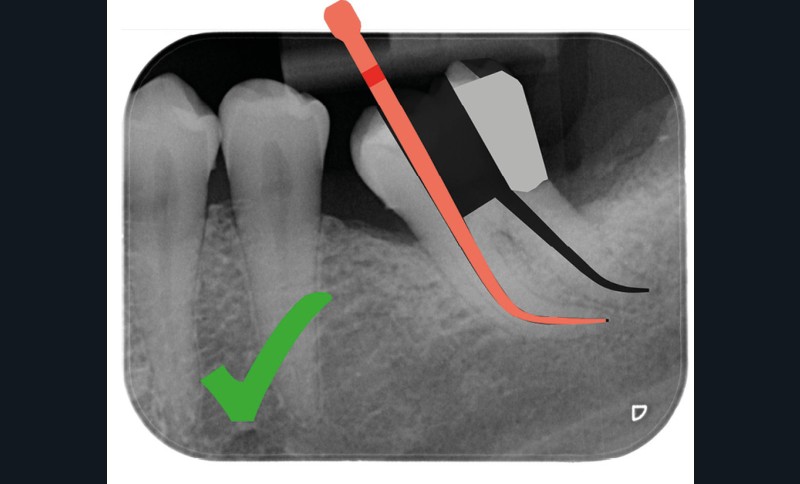

Aussi petite que possible, aussi large que nécessaire

Une cavité d’accès moderne, dictée par l’anatomie et la pathologie de la dent, optimiserait à la fois les pronostics endodontiques et biomécaniques et donc la longévité de la dent sur l’arcade (patient-centered dentistry ou dentisterie centrée sur le patient) (fig. 5).